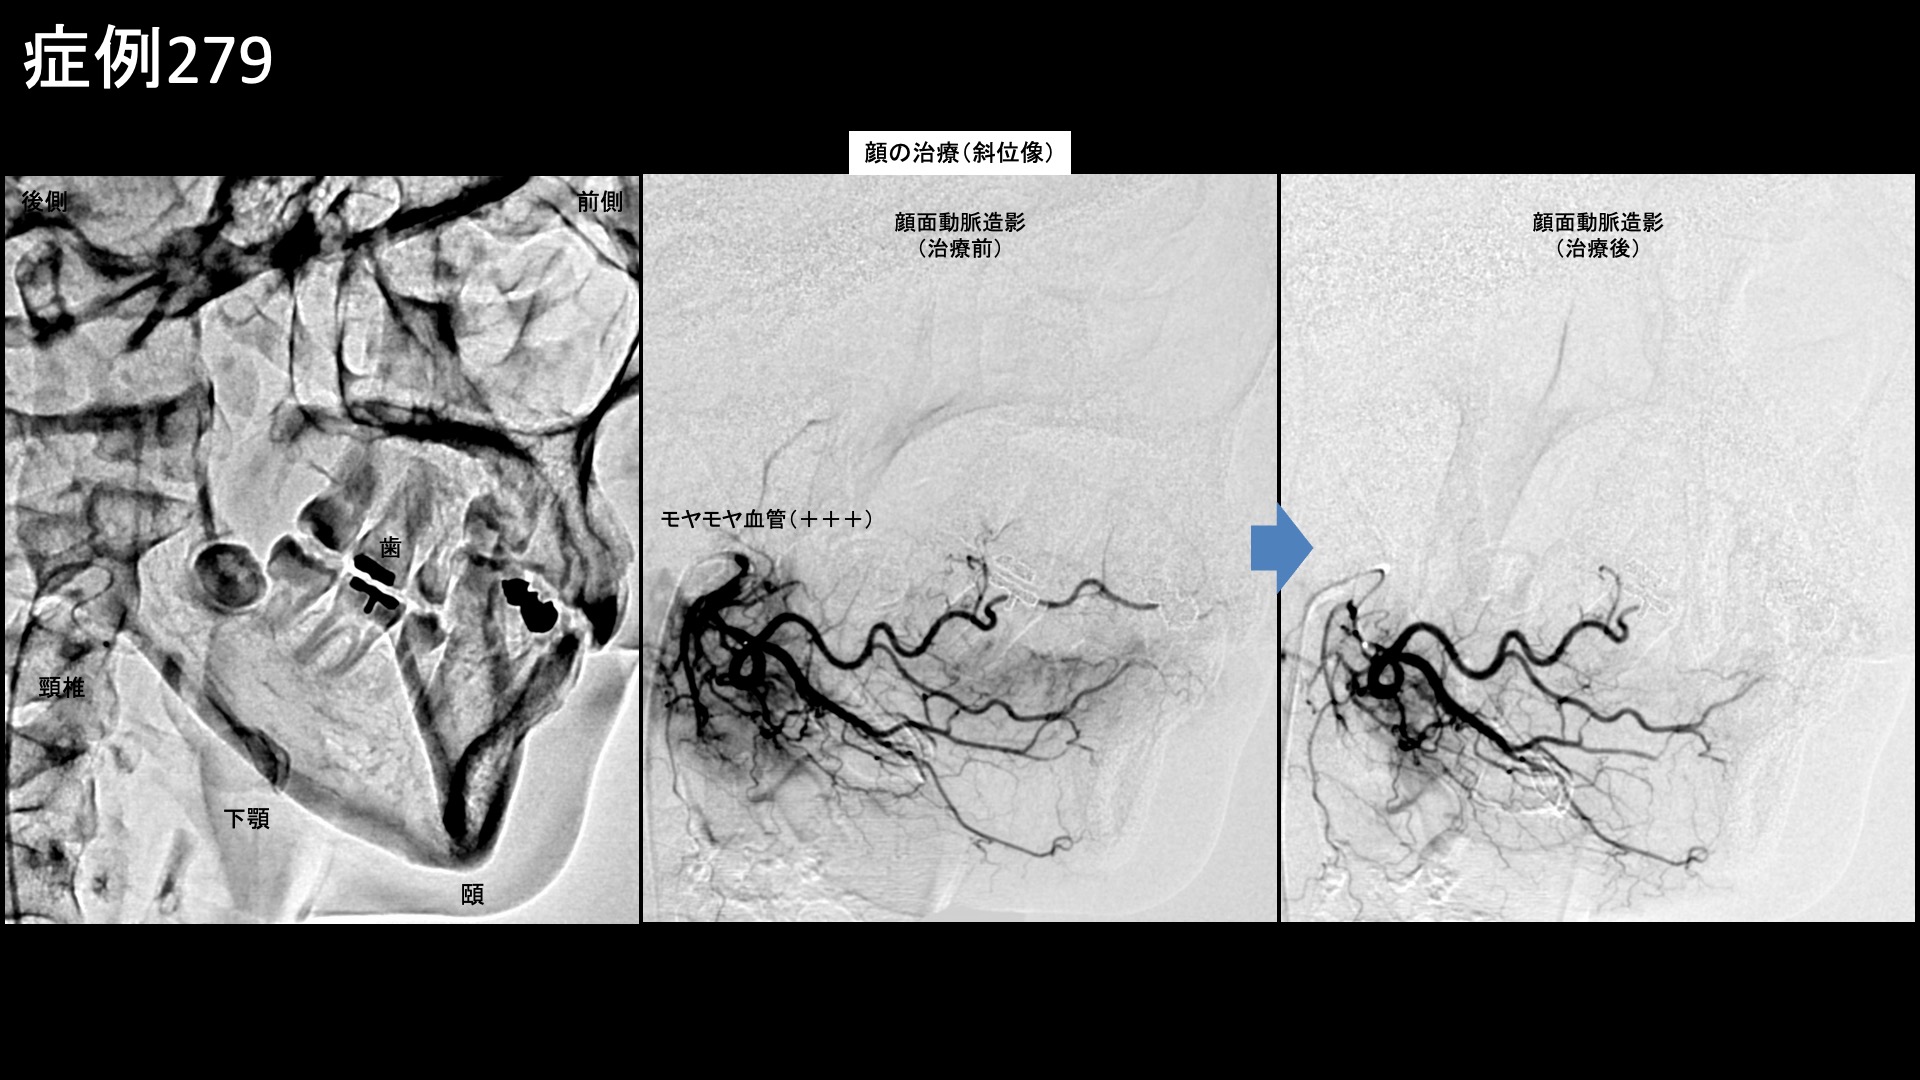

顎や口の周囲などに分布する顔面動脈、頬の主要責任血管である顎動脈で特にモヤモヤ血管が濃染像として描出されました。治療後は画像上速やかに消失しました。その他複数箇所の治療を行い終了しました。

治療前画像:損傷を受ける、あるいは繰り返しのストレスにより発生した異常な新生血管

治療後画像:カテーテルを用いて塞栓物質を血管内に投与し新生血管を塞いだ状態